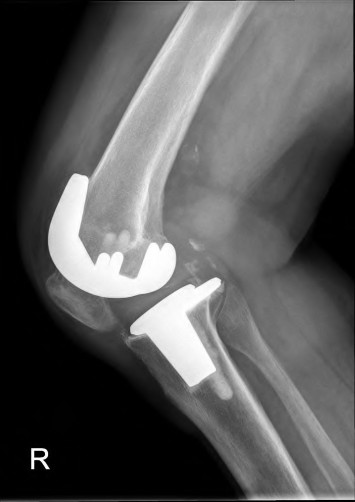

Question 15

During a revision total knee arthroplasty, removal of the tibial component reveals a massive contained metaphyseal defect measuring 3 cm deep, but with an intact cortical rim. According to the Anderson Orthopaedic Research Institute (AORI) classification, what type of defect is this, and what is the preferred method of management?